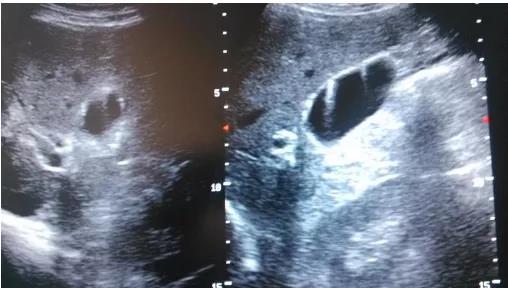

①看真假:真正可能變癌的是真息肉,假息肉不用管;